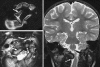

Background: The embryology of the bony craniovertebral junction (CVJ) is reviewed with the purpose of explaining the genesis and unusual configurations of the numerous congenital malformations in this region. Functionally, the bony CVJ can be divided into a central pillar consisting of the basiocciput and dental pivot and a two-tiered ring revolving round the central pivot, comprising the foramen magnum rim and occipital condyles above and the atlantal ring below. Embryologically, the central pillar and the surrounding rings descend from different primordia, and accordingly, developmental anomalies at the CVJ can also be segregated into those affecting the central pillar and those affecting the surrounding rings, respectively.

Discussion: A logical classification of this seemingly unwieldy group of malformations is thus possible based on their ontogenetic lineage, morbid anatomy, and clinical relevance. Representative examples of the main constituents of this classification scheme are given, and their surgical treatments are selectively discussed.